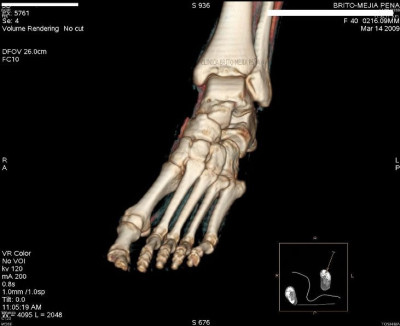

Pié normal anterior

Pié normal posterior